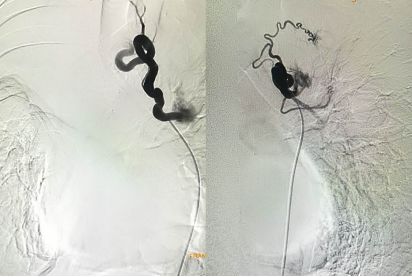

诊断支气管扩张30年,咯血两周。造影发现左右侧支气管动脉迂曲扩张。

治疗前

介入栓塞后,支气管动脉不再向肺内供血,咯血停止。

治疗后